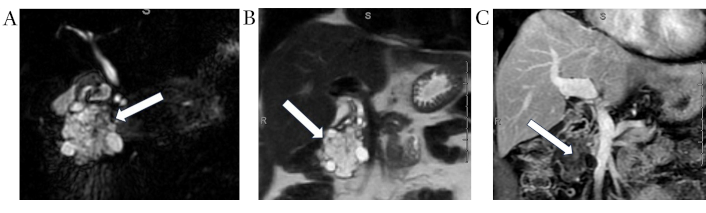

On MRI, SCAs appear as a cluster of small cysts grouped together within the pancreas (Figure 2A). Signal characteristics are as follows: Cystic foci demonstrate hyperintensity on T2 (Figure 2B), hypointensity on T1 (Figure 2C) and the central fibrous scar is hypointense on T2, T1 C+ (Gd): on delayed contrast enhanced imaging, the fibrous septa between the cysts appear enhanced [41].

Serous cystadenoma. Coronal MRCP (A) and coronal T2 weighted (B) images demonstrate a large lobulated multilocular cystic lesion (white arrows) with honey-combed appearance in the pancreatic head. Corresponding post-contrast coronal T1 weighted image (C) demonstrates numerous internal thin enhancing septations (white arrow). MRCP: magnetic resonance cholangiopancreatography